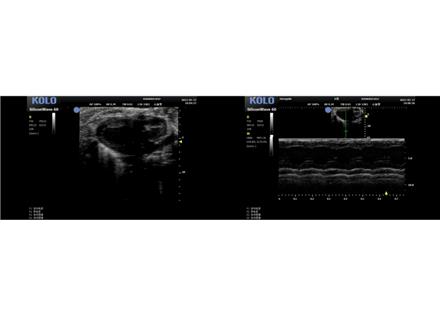

小動物 B 超

檢測能力:觀察小動物的心血管、腹部臟 器、淺表組織及胚胎等提供了清晰多彩的超聲圖像

察小動物的心血管、腹部臟 器、淺表組織及胚胎等提供了清晰多彩的超聲圖像。 系統(tǒng)的實時無創(chuàng)操作也為科研實驗 的反復(fù)驗證,長期動態(tài)觀察等提供了極大的 便利性。

心臟方面的研究 1 左心室長軸 2 左心室短軸 3 四腔心

血管方面的研究 1 腹主動脈 2 主動脈弓 3 頸動脈 4、內(nèi)臟 5 腫瘤